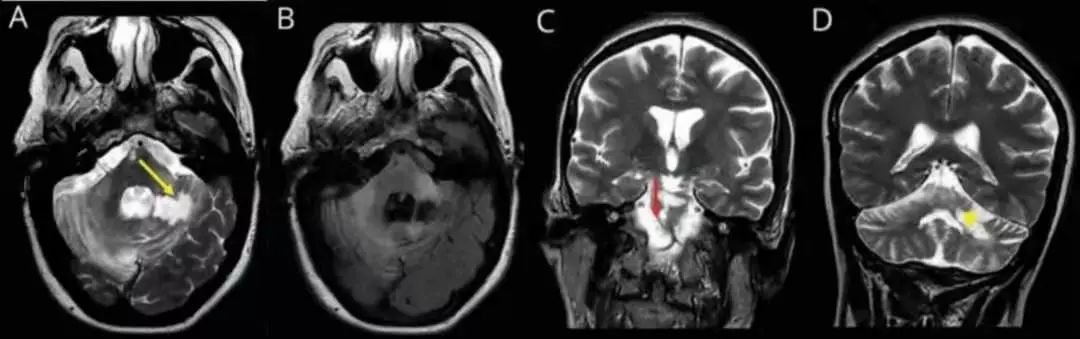

答案:肥大性下橄榄核变性(HOD)。

注:图左侧为患者复诊MRI放大图,右侧示齿状核—红核—橄榄核通路即Guillain‐Mollaret 三角。

完整的Guillain‐Mollaret 三角由一侧齿状核、对侧红核和对侧下橄榄核组成。齿状核的神经纤维经小脑上脚,交叉后到达对侧红核,红核发出的神经纤维到达同侧的下橄榄核,下橄榄核再发出神经纤维经小脑下脚到达对侧小脑皮质,继而投射到小脑齿状核。肥大性下橄榄核变性(HOD)的发病机制主要是齿状核—红核—橄榄核环路的破坏,常见的病因有海绵状血管瘤、手术、出血、梗死、肿瘤、外伤、炎症、脱髓鞘、变性疾病及放射性损伤等。原发病灶常位于中脑、脑桥或小脑。脑梗死是 HOD 的常见病因。HOD最核心的临床特点:Guillain‐Mollaret 三角上的原发病变(DTI和DTT可显示格莫三角环路破坏)、迟发性特征性症状(如腭肌阵挛、眼震、复视、共济失调、肢体阵挛等)、下橄榄核增大且T2WI、FLAIR序列上呈高信号。当 Guillain‐Mollaret 三角受损之后,下橄榄核的神经元失去了上游神经元的抑制从而出现异常活动,患者常表现出腭肌阵挛、眼震、复视、共济失调、肢体阵挛等特征性症状。腭肌阵挛是 HOD 的代表性体征,但并非出现在所有病例中。